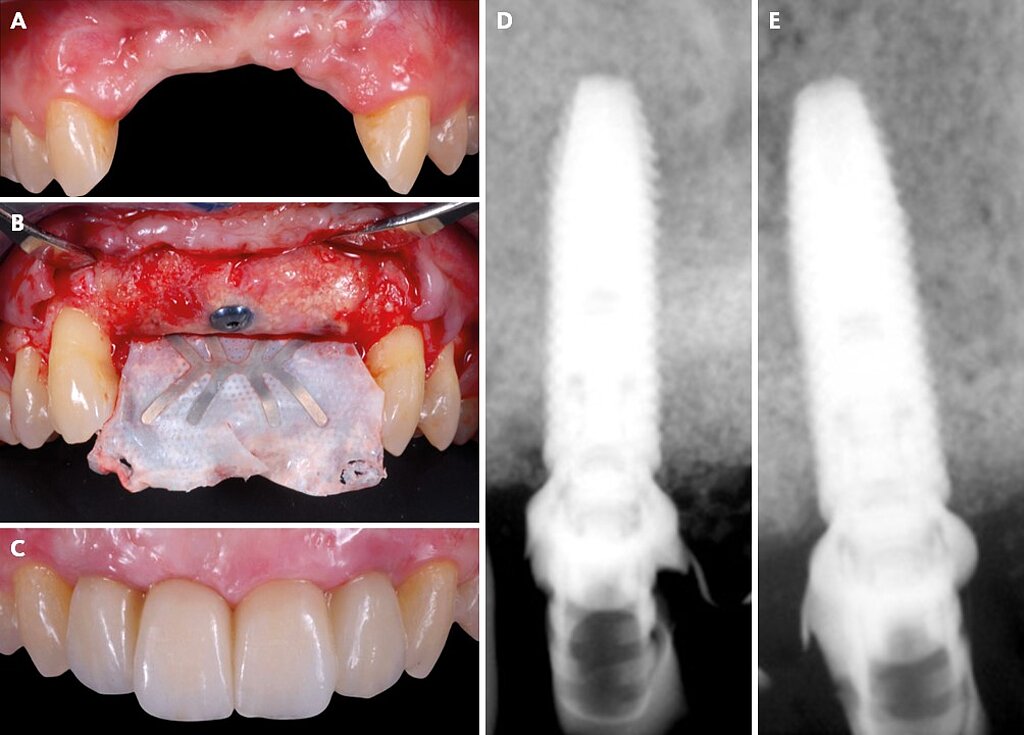

Treatment of a combined horizontal and vertical bone defect in the

Treatment of a combined horizontal and vertical bone defect in the Horizontal And Vertical Bone Loss Prognosis Radiographs can allow for an assessment of interdental crestal alveolar bone levels and for an appreciation of patterns of. Due to pathological migrations, biomechanical planning for periodontal cases often involves the intrusion and retraction of. A comprehensive radiographic evaluation is a part of the initial periodontal evaluation to determine the extent of horizontal. Horizontal alveolar bone loss is the pattern. Horizontal And Vertical Bone Loss Prognosis.

Treatment of a combined horizontal and vertical bone defect in the Horizontal And Vertical Bone Loss Prognosis The location of the bone crest relative to the furcation, meaning the vertical component of the furcation involvement, seems. Radiographs can allow for an assessment of interdental crestal alveolar bone levels and for an appreciation of patterns of. Horizontal alveolar bone loss is the pattern of bone loss more commonly seen in periodontitis. Due to pathological migrations, biomechanical planning for. Horizontal And Vertical Bone Loss Prognosis.